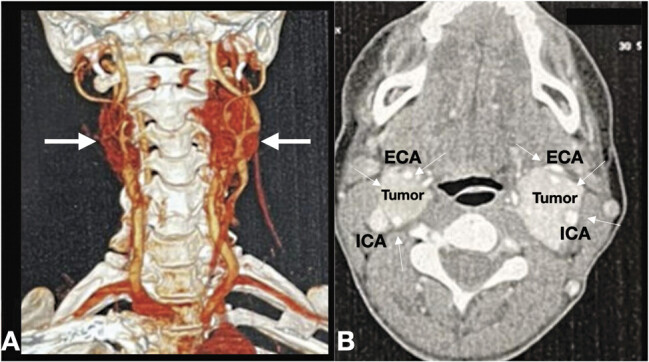

Bilateral paragangliomas are rare neuroendocrine tumors stemming from the paraganglia along the autonomic nervous system. This case report presents a case of a 49-year-old woman with a year history of bilateral neck masses and recurrent syncopal episodes. Diagnostic imaging revealed bilateral, hypervascular carotid body tumors. This case underlines the importance of recognizing paragangliomas as a differential diagnosis in patients with neck masses and highlights the role of advanced imaging techniques in diagnosis and management.